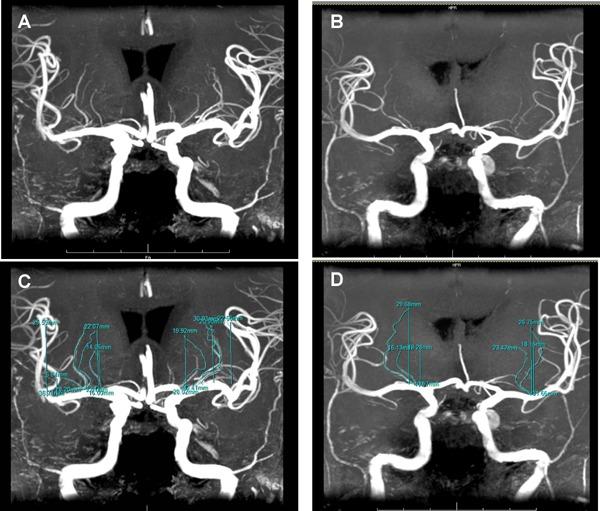

Twenty-five subjects with type 2 diabetes and 25 non-diabetic control subjects underwent 7 Tesla (7 T) brain MRI. The prevalences of SVD and LSA structural changes were determined in each group.

SVD prevalence did not differ significantly between the type 2 diabetes and control groups. The average numbers of stems, as well as numbers of branches, of LSA were significantly smaller in diabetic subjects than non-diabetic control subjects. The signal intensity of LSA was markedly decreased, indicating reduced blood flow in type 2 diabetes.

In spite of the prevalence of SVD being similar, structural changes and decreased signal intensity of LSA were highly detected in diabetic subjects compared with non-diabetic controls, suggesting that 7 T MRA enables us to determine LSA impairment prior to the development of SVD. Early detection of LSA impairment allows us earlier interventions aimed at the prevention of atherosclerotic events.

25 例 2 型糖尿病患者和 25 例非糖尿病对照组受试者接受了 7 特斯拉(7T)脑 MRI 检查。确定了每组 SVD 和 LSA 结构变化的患病率。

2 型糖尿病组和对照组的 SVD 患病率无显著差异。LSA 的干数和分支数在糖尿病患者中明显少于非糖尿病对照组。LSA 的信号强度明显降低,表明 2 型糖尿病患者的血流量减少。

尽管 SVD 的患病率相似,但与非糖尿病对照组相比,糖尿病患者的 LSA 结构变化和信号强度降低更为显著,提示 7T MRA 能够在 SVD 发生之前确定 LSA 损伤。早期发现 LSA 损伤可以更早地进行干预,以预防动脉粥样硬化事件。